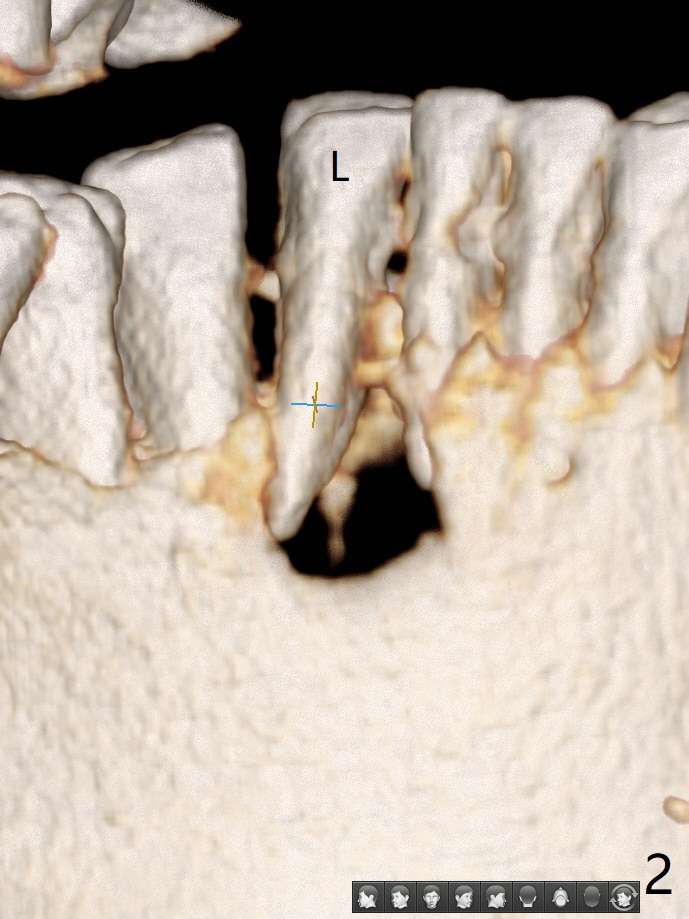

A 73-year-old woman has discomfort associated with #23 four months post Class V composite at #23-25 (Fig.1 C (*: Class V lesions)). Bone loss seems to be more severe lingually, especially at the crest (Fig.2 L). It appears that the apex of the tooth #24 is also in the large apical lesion (Fig.3). Class V composite is apparently continuous with the pulp at #25,24,23 (Fig.5-7). In contrast, Class V defect does not involve the pulp at #26 (Fig.4). If necrosis is confirmed clinically for #23 24 and 25, RCT will be conducted. Due to 7-day Amoxicillin taken for #3 implant, the patient feels that her tongue moves freely, as related to reduction in pain and swelling lingual to #23 (Fig.8 *). Endo ice test shows necrosis of #23 to 25. RCT is initiated at #23 (Fig.9) with buccal and lingual swelling. Endo may have to be at #24 with apicoectomy with PRF. The lingual swelling remains at #23, although there is no pain or purulent discharge 5 and 5.5 months post debridement (Fig.10,11). RCT is finished (Fig.12). Apicoectomy is pending with PRF. Less aggressive curettage will be done at #24 to maintain apical blood supply. Vitality tests have been done without conclusion.